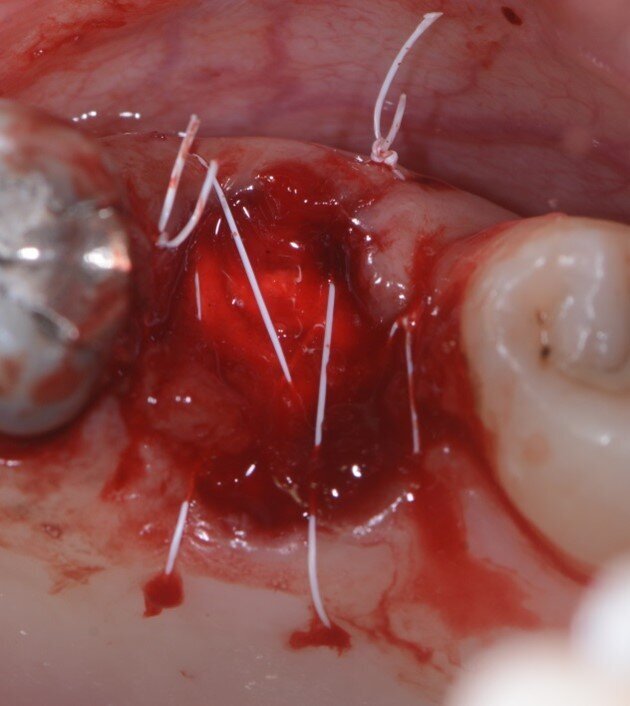

Fig. 6 - Spugna di collagene e suture.